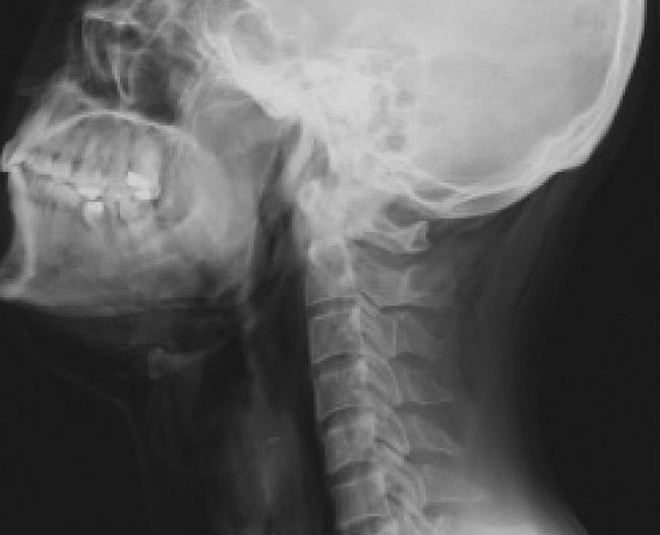

इलेक्ट्रॉनिक उपकरण इस्तेमाल करते समय लिए गए एक्सरे से पता चलता है कि महिलाओं की गर्दन और जबड़े में पुरुषों की तुलना में ज्यादा दर्द क्यों होता है।